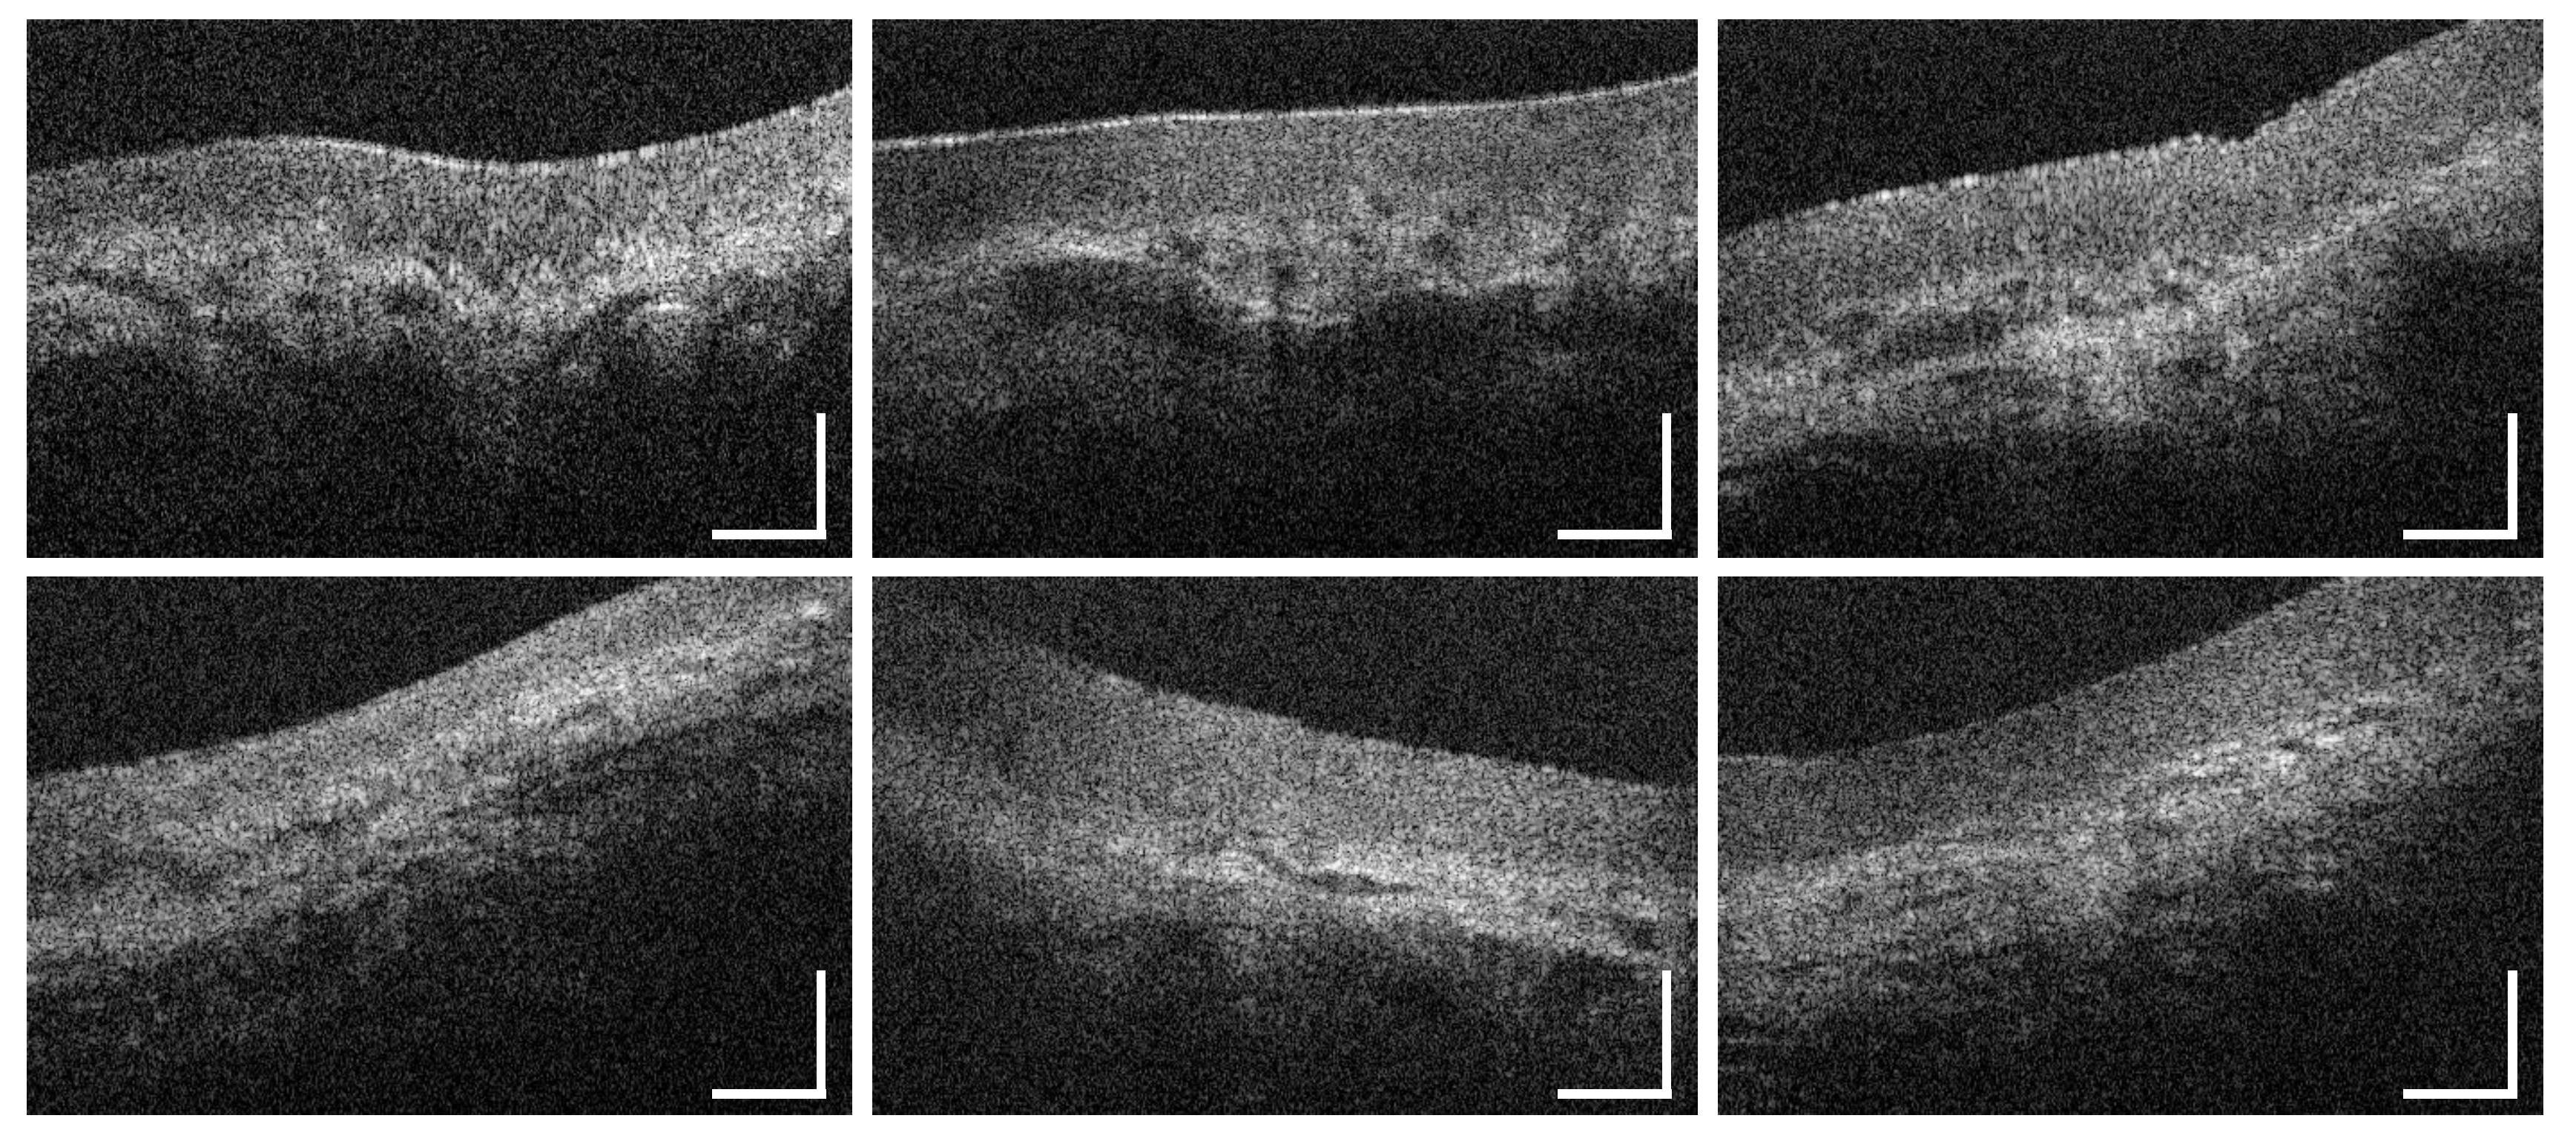

3.1. Labial and Alveolar Mucosa

3.2. Buccal Mucosa

3.3. Sublingual Mucosa

3.4. Hard Palate

3.5. Soft Palate and Oropharynx